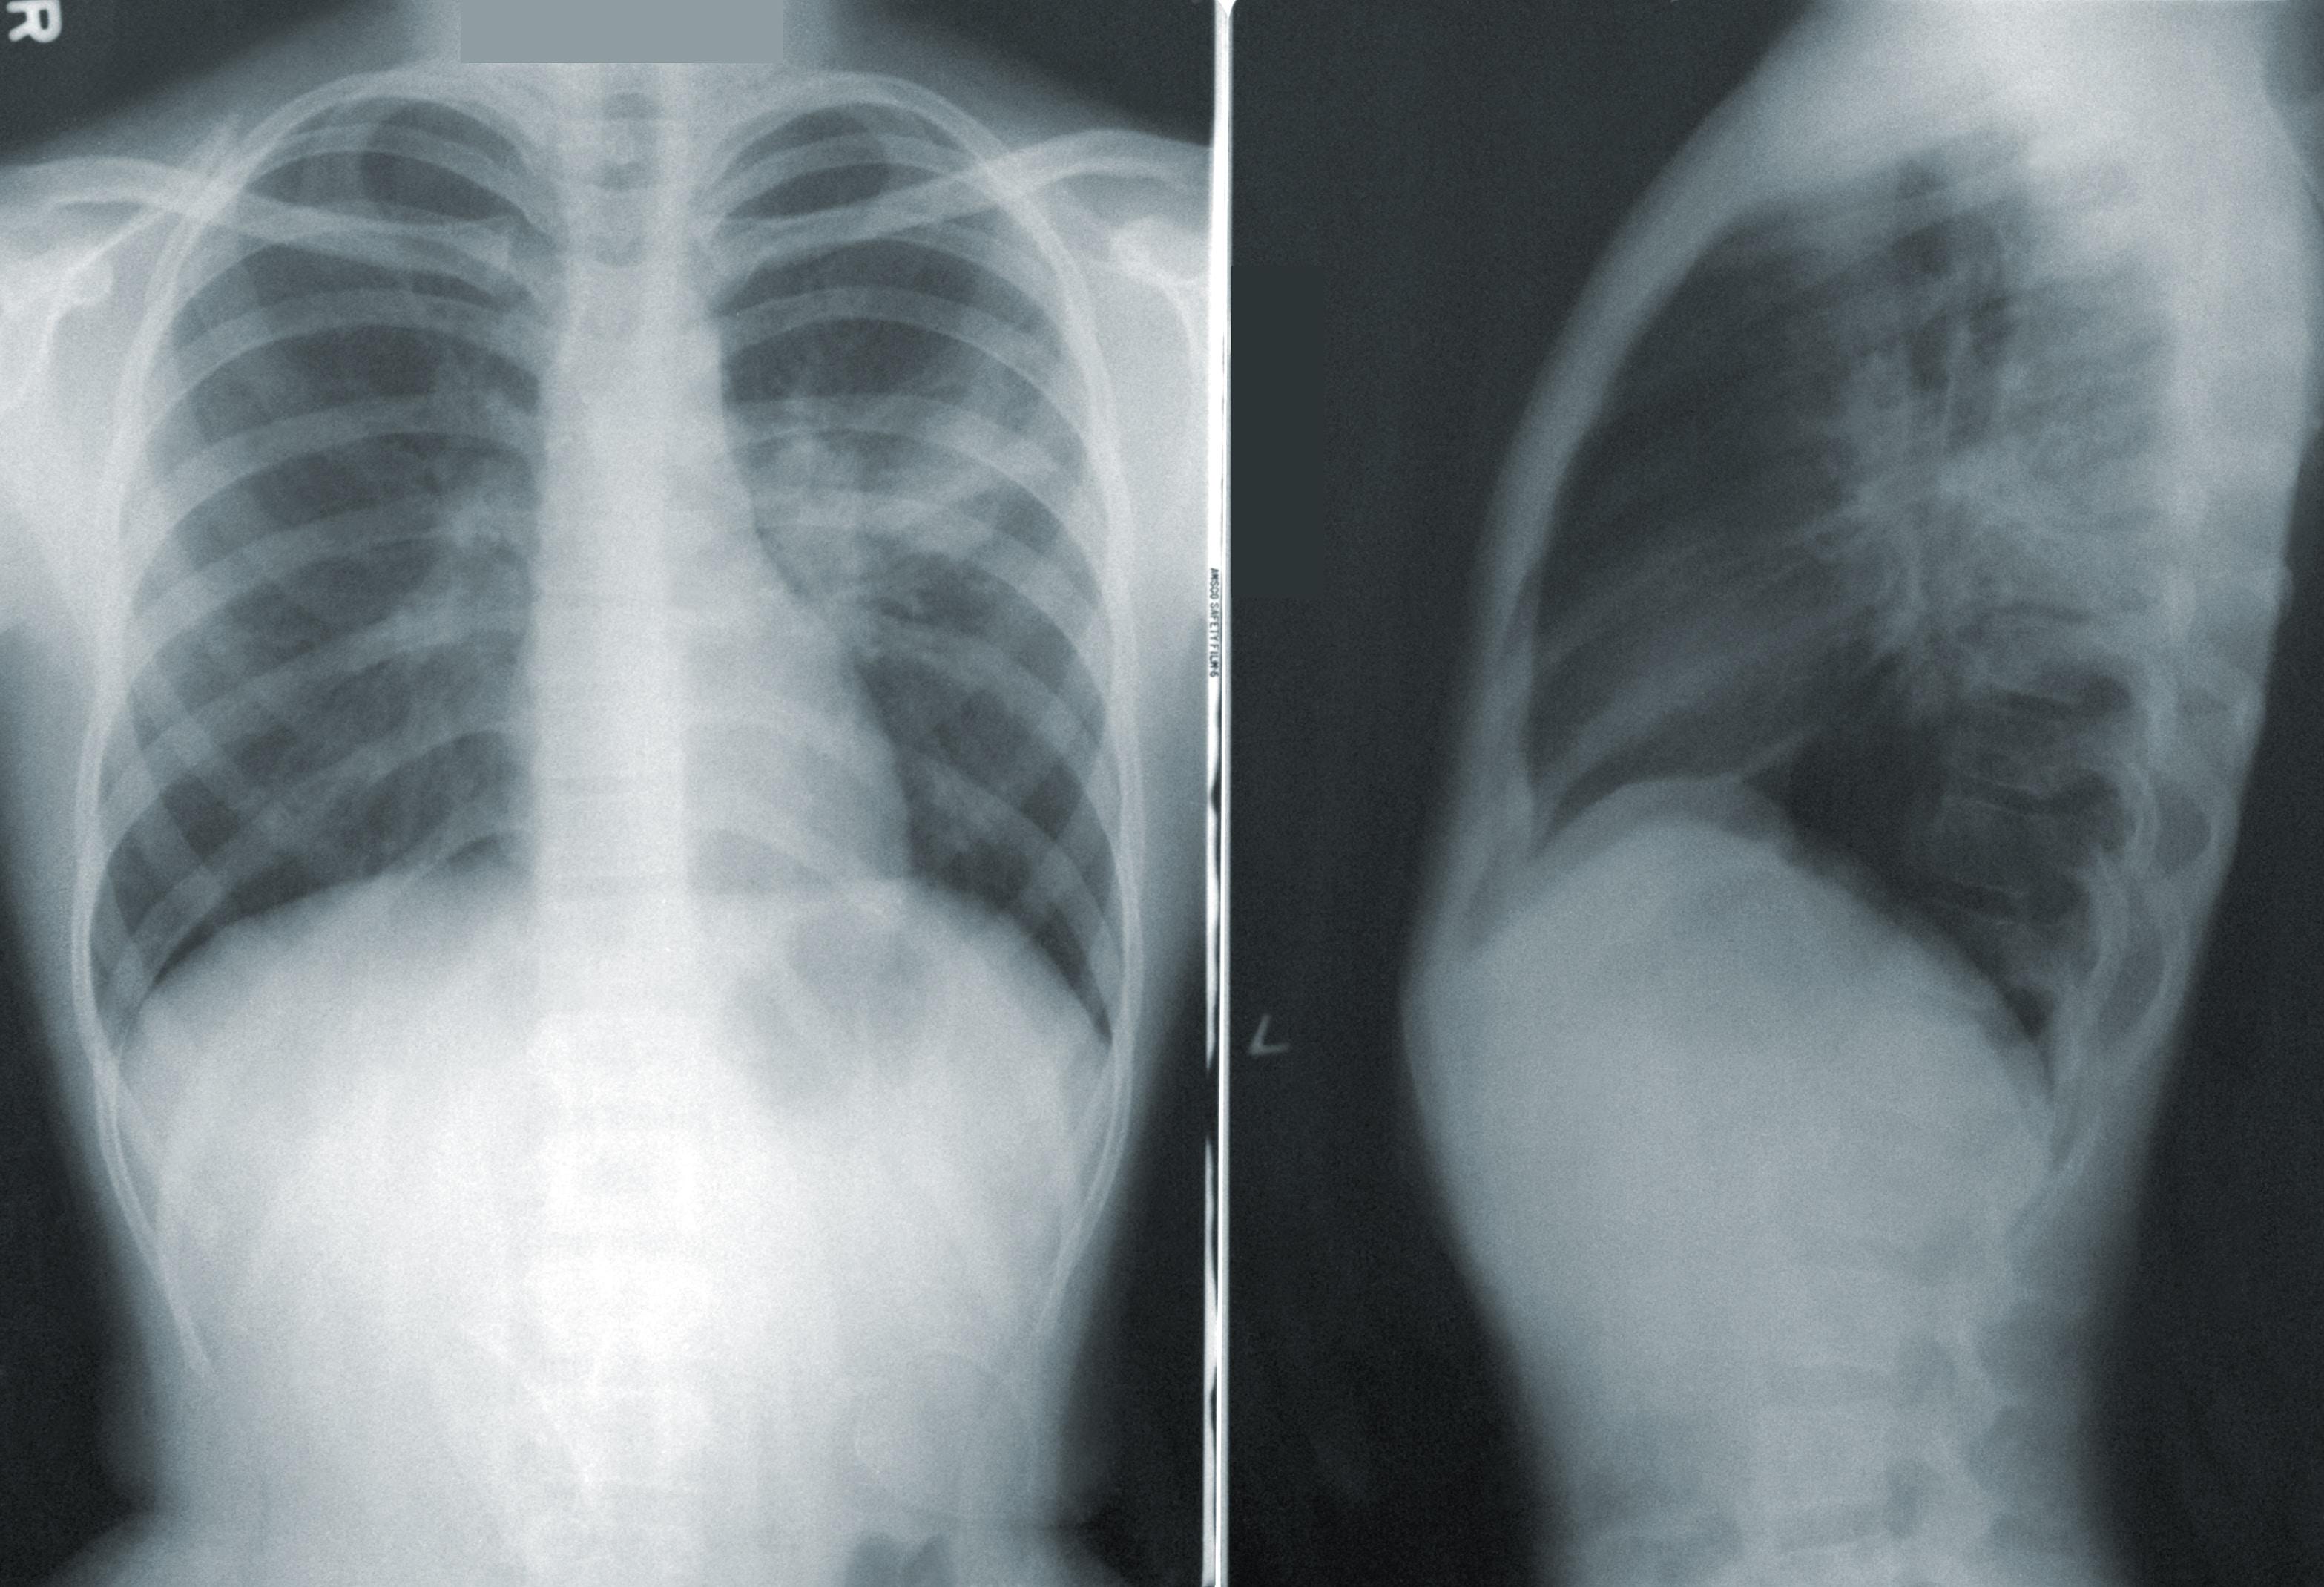

Bronchoskopia jest jednym z podstawowych badań wykonywanych w pulmonologii. Pozwala na dokładne zobrazowanie dróg oddechowych, wykrycie patologii oraz pobranie próbek do dalszych badań. W tym artykule przedstawimy, czym jest bronchoskopia, jak się do niej przygotować oraz czy jest bolesna.